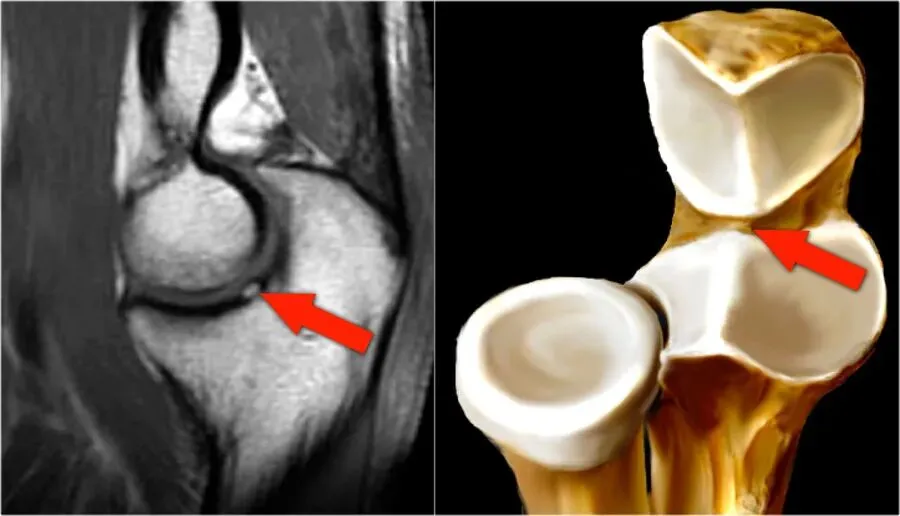

外侧副韧带复合体

A 图:完整的环状韧带,起自并止于尺骨半月切迹(分别用箭头和箭头头标注),环状韧带环绕桡骨头外周(* 标注)。B-D 图:完整的外侧尺侧副韧带(C、D 中 * 标注)和桡侧副韧带(B 中箭头标注);外侧尺侧副韧带从外上髁(LE 标注)延伸至尺骨的旋后肌嵴(SC 标注);桡侧副韧带从外上髁延伸至环状韧带;外侧尺侧副韧带环绕桡骨颈后方;桡侧副韧带位于外侧尺侧副韧带前方;可见共同伸肌肌腱(B 中箭头头标注)。